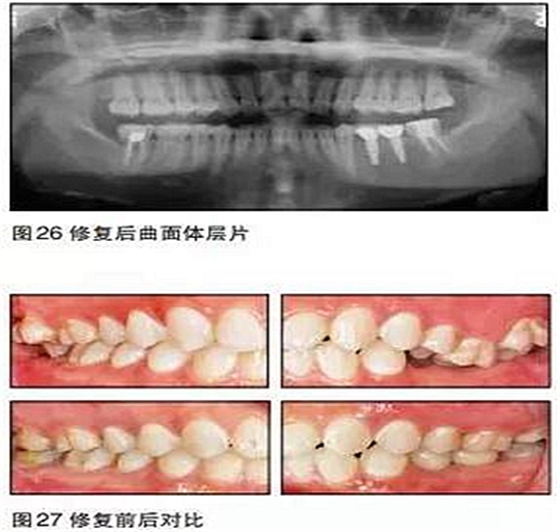

在本病例中,患者的主觀愿望是想通過(guò)種植來(lái)修復(fù)缺失牙。口內(nèi)檢查及口腔曲面體層片顯示患者缺牙區(qū)的骨質(zhì)良好,骨量充分,但咬合情況非常復(fù)雜。如果不先通過(guò)正畸治療來(lái)改善咬合而直接進(jìn)行種植手術(shù),那么后期的修復(fù)將異常困難。

35、36種植時(shí)采用骨水平的NobelActive植體;由于植體位置比較理想,修復(fù)體采用螺絲固位的氧化鋯基臺(tái)一體冠,便于今后牙冠及種植體的維護(hù)。最終種植修復(fù)完成后在咬合、美觀、牙齦乳頭充盈等方面都取得了滿意的效果。